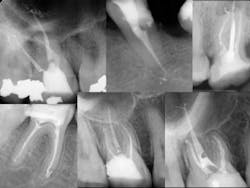

Once all of the canals are found, I will go through the series of Sybron Twisted Files size 25 tapering from 0.10 to 0.80 to 0.60 to 0.40. The 0.40 file should reach the working length for most canals. On a large palatal or distal canal, the 0.60 TF will usually reach working length. After which, using the crown-down technique with the Brasseler EndoSequence rotary files, instrument each canal until files reach the working length. Once instrumentation is complete, take a P.A. with gutta-percha to confirm instrumentation to working length. I find it much easier to take working length films with gutta-percha rather than files (which may fall out, bend, or separate)

- Separated file — The dreaded separated file is probably the most common complication clinicians encounter when performing root canals. There was a time when those broken instruments made me wish I never started the root canal in the first place. These days, I will work to bypass the file and get a predictable result.

If a file separates, take a P.A. film immediately to figure out where in the canal the file is lodged. Most likely there’s a curve that the file could not negotiate. Start negotiating the canal with a 6 or 8 C-file. The goal is to engage the space around the file where you can instrument next to it. It could take an extra 30 or 40 minutes and lots of irrigation, but you should be able to negotiate the canal with a 15 file to working length. Irrigate very well and obturate. Sometimes the file will actually exit the orifice of the tooth when irrigating. But it’s perfectly reasonable to use the file as part of the fill.